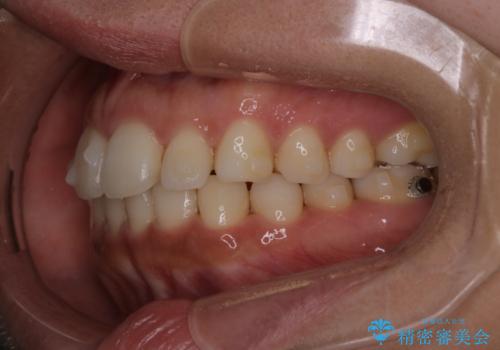

【インビザライン】前歯の後戻りを再矯正

- 前歯が出ていることを主訴に来院されました。検査の結果、口元が標準より出ているわけではなかったため今回はIPRと拡大をし、非抜歯で治療を行いました。

非抜歯でも歯軸の向きを改善したことで前歯が下がり、出っ歯に見えてしまうという主訴が改善しました。